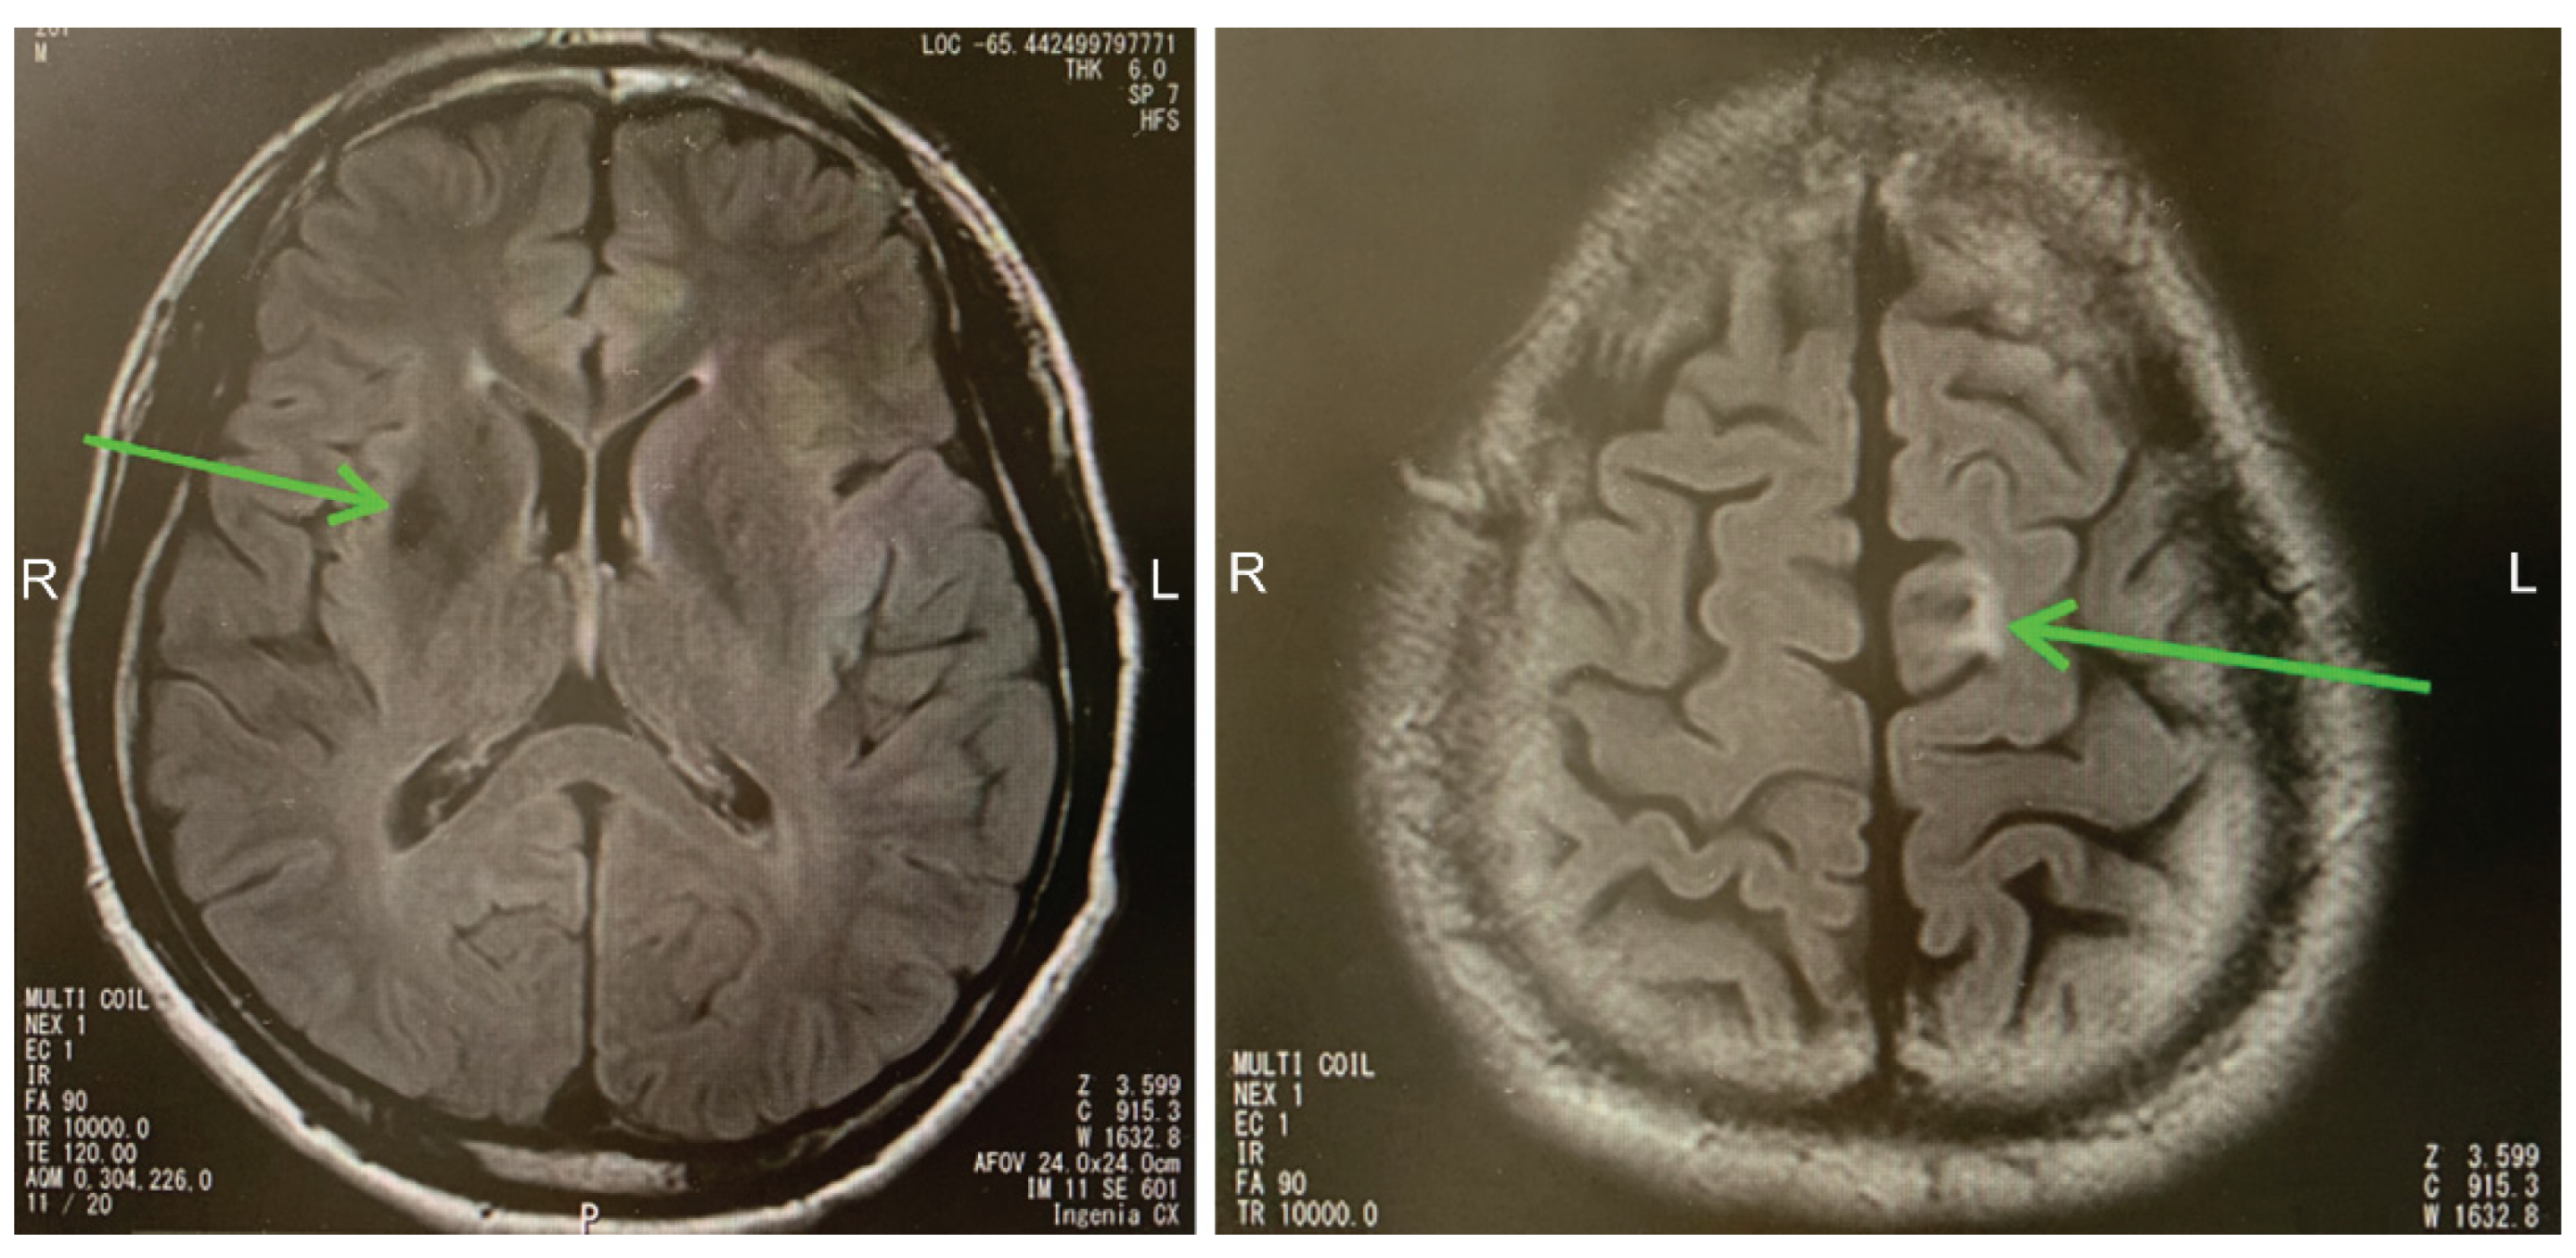

2.2. Case 2